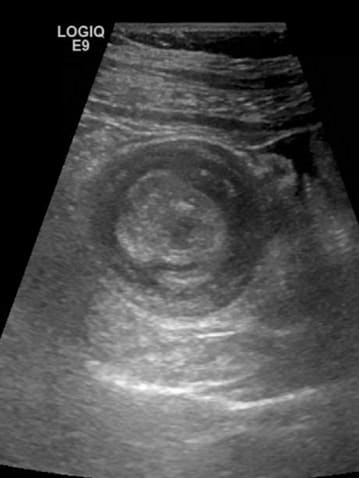

A ultrassonografia irá mostrar duas imagens ecogênicas circunscritas. Representam o corte transversal de uma alça no interior da outra e é chamado de imagem em alvo.